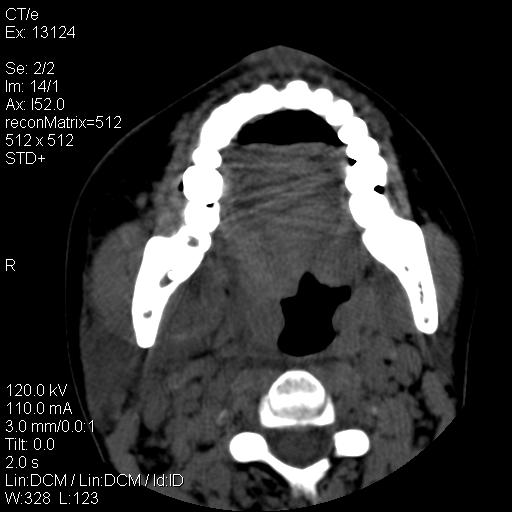

标题: CT18257:女,29岁,右下磨牙痛 [打印本页]

标题: CT18257:女,29岁,右下磨牙痛

女,29岁,右下磨牙痛,因产后2月,故未治疗。现右颌肿痛伴张口困难。请大家看看右侧鼻咽部、口咽部是否

1.考虑右侧下颌区脓肿(牙源性)

考虑右下智齿冠周炎伴周围软组织炎症,脓肿形成

1)考虑右侧下颌区软组织脓肿(牙源性)。2)鼻咽部炎性改变;建议追踪复查。3)右侧上颌窦炎。4)双侧下鼻甲黏膜肥厚。